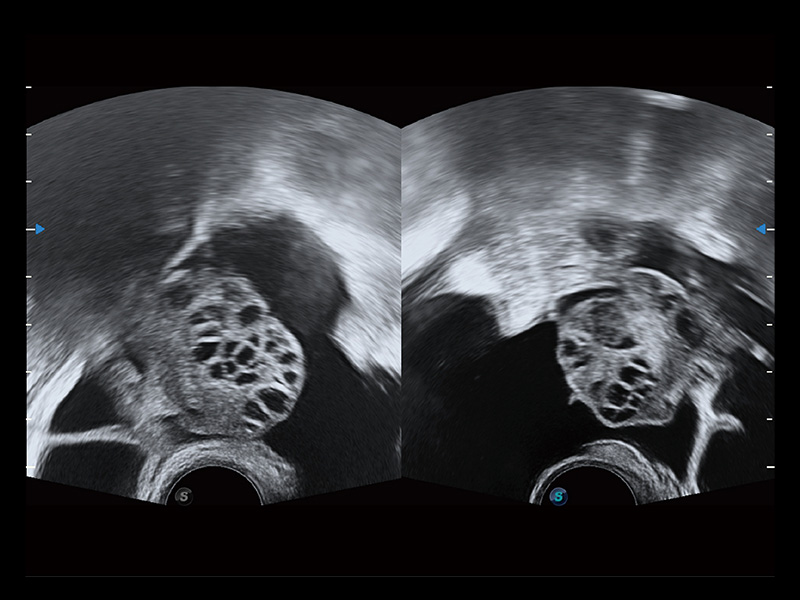

临床图

卵巢多囊样改变